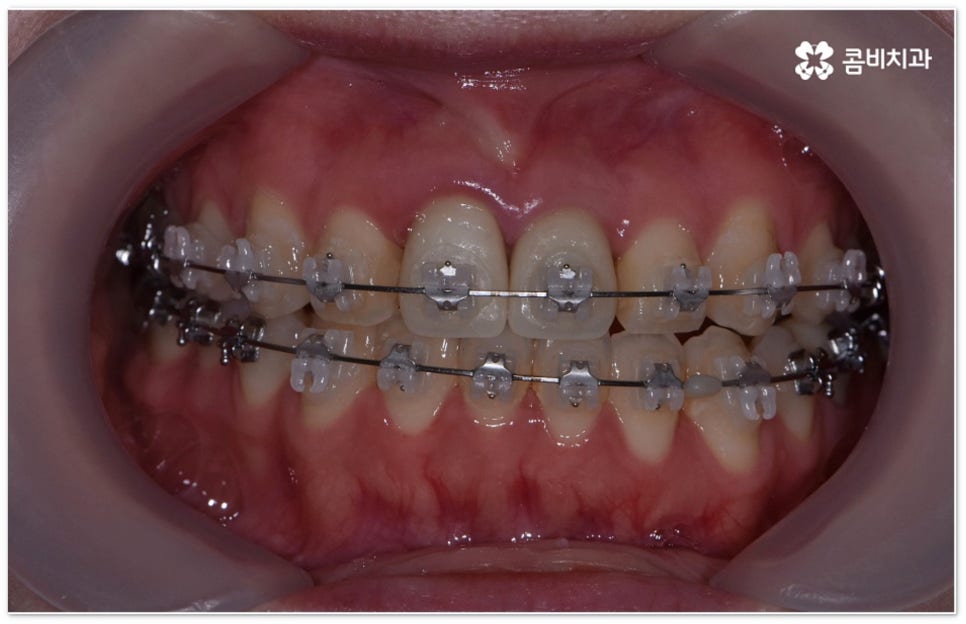

요즘 가장 많이 쓰이는 치아교정장치 인 클리피씨는 치아 색상의 세라믹 브라켓을 이용하기 때문에 심미성도 뛰어나고 자가결찰방식을 이용하여 보다 적은 힘으로 지속적이고 부드러운 치아 이동을 할 수 있도록 고안된 장치이므로 통증을 줄여줄 뿐 아니라 보통 2년 남짓 걸렸던 전체 교정 기간 역시 6개월 정도 감소시켜 줄 수 있습니다. 환자분들의 상황에 따라 내원 횟수 역시 줄일 수 있기 때문에 업무가 많이 바쁜 직장인분들의 경우에도 이용할 수 있다는 장점을 가지고 있어요.